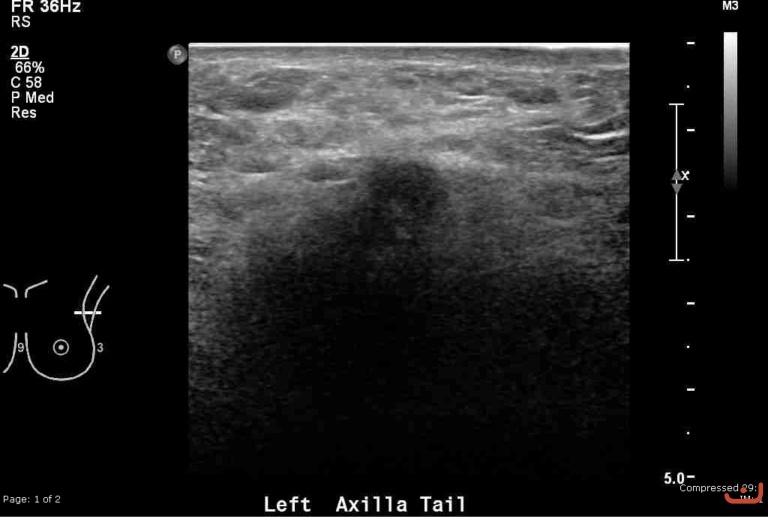

Malignant solid mass

Thursday, 30 April 2015

141.15 KB (768 x 517 px)